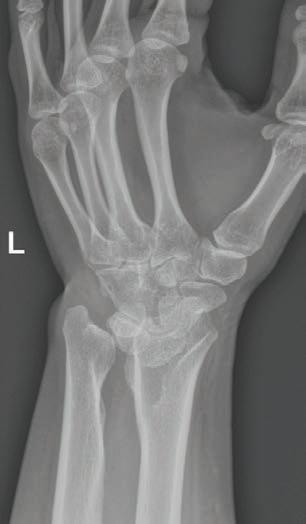

Enfermedad rara de la placa de crecimiento radial en un adulto joven que responde a terapias ‘Deformidad de Madelung’: Informe de caso.....................................................................37

Colaboradores: